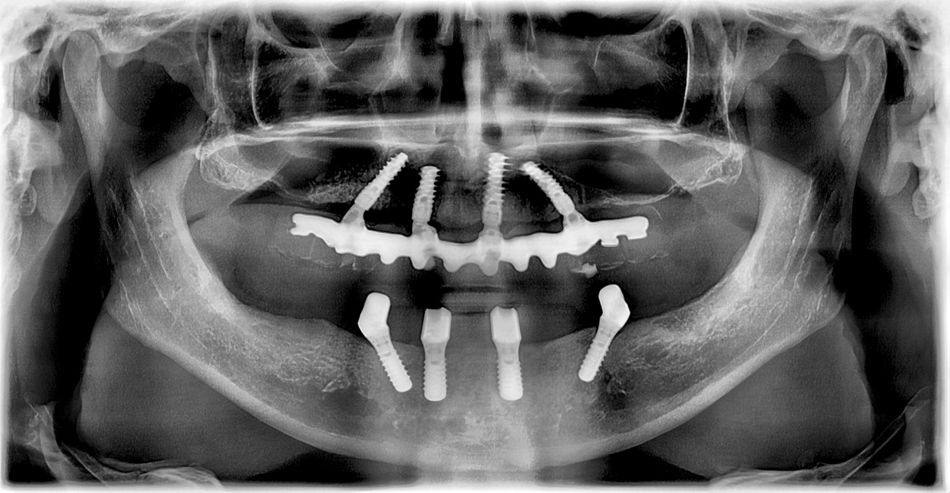

The preoperative panoramic X-ray showed that both maxillary sinuses expanded widely towards the anterior segment, so that the base of the premaxilla was very narrow. Coincidentally, a mesiodens was found apically to the region of tooth 21. The treatment plan involved the removal of the remaining teeth (#11,23,24,25) plus the mesiodens, the placement of four BLX implants in the same operation, followed by immediate loading per the Pro Arch concept. In view of the reduced space in the base of the premaxilla, as well as the discovery of the mesiodens, it was necessary to use a surgical template (designed with CoDiagnostix) after a CBCT scan so that the implants could be placed in the correct three-dimensional position. The manufacturing of the provisional bridge was planned in a part-digital, part-analog procedure using the Trios® intraoral scanner (3-Shape) with the Dental Wings Software, supplemented by a cast model after taking a conventional impression.